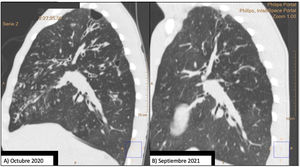

Comparison of 2 sagittal chest CT reconstructions. Image (A) shows a thin-walled cystic lesion (bulla), extensive bilateral bronchiectasis, with significant thickening of the bronchial walls and a tree-in-bud pattern. After 1 year of treatment with elaxacaftor/tezacaftor/ivacaftor, image (B), bronchiectasis is significantly improved and the apical bulla is resolved.

Given the patient's clinical situation, he was enrolled in an early access program for treatment with CFTR modulators, a compassionate use program known as MyMAPs. In October 2020, treatment began with elexacaftor/tezacaftor/ivacaftor (ETI) 75/50/100mg, 2 tablets at breakfast and 1 tablet of ivacaftor 150mg at dinner. After 1 year of follow-up, the patient had improved significantly. Lung function had increased by 25% (FEV1: 2450ml, 55.8%), respiratory exacerbations had dramatically reduced – no events since the start of treatment – cough and bronchorrhea had resolved, and exercise tolerance had improved. Follow-up chest CT showed a significant improvement in mucus plugging, a significant reduction in the size and number of bronchiectasis, some of which had disappeared (Fig. 1B), and a reduction in the size of the bulla in the right upper apex (Fig. 2B). The Bhalla score increased from 6 to 17 points in September 2021. The patient was therefore taken off the lung transplantation waiting list.